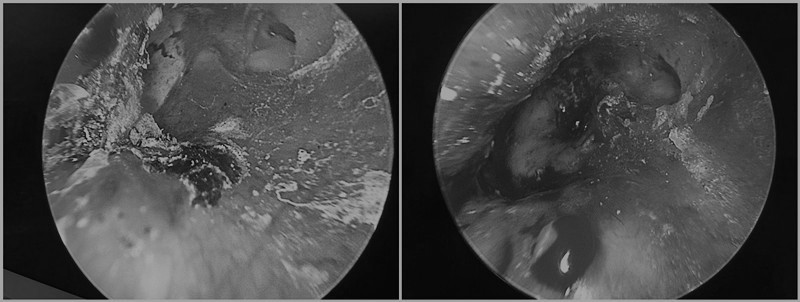

三天后的周一,在熟人推荐下,老舒挂了王鑫主任的专家号。门诊的内镜下,王主任发现老舒的外耳道肿得特别厉害,深方看见了水泥。水泥结成了硬块,硬块的边缘紧紧裹着外耳道的皮肤,更不幸的是,鼓膜的一大半都被水泥紧紧地贴着,轻轻的碰一下,就有穿孔的风险!

手术中,王鑫主任在耳内镜下用纤维耳器械小心翼翼在鼓膜边缘,轻轻取下那块水泥——真是如履薄冰呀,鼓膜被水泥烧伤,变得很薄,终于在没有损伤鼓膜的情况下,把水泥拿出来了。手术室的医生,麻醉师,护士们也长长地舒了一口气!几天之后,老舒又来门诊复查,结果是鼓膜保住了,听力也恢复了!老舒高兴地连声致谢!